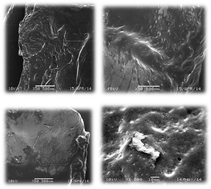

Differential scanning calorimetry (DSC) and thermogravimetric (TGA) investigations, acetate electrophoresis (CAE), Fourier-transform infrared spectrometry (FTIR), scanning electron microscopy (SEM) analysis and microbiological procedures were all carried out after heating the samples to a temperature sufficient for simulating a burn incident. In particular, the purpose of the present study was to analyze the effect of antioxidants, such as fucoidan from brown seaweed and flame-retardant cyclic organophosphates and phosphonates, on an organic chicken skin that gets changed by a burn incident. DSC was considered to be a useful tool in assessing in vitro temperature-mediated cross-linking; an innovative analytical conclusion was obtained from the experimentation described in the paper. FTIR tests revealed that heating a dry organic chicken skin to the boiling point leads to the disappearance of a wide band in the 1650–1550 cm−1 area or the conversion of a band, which may be attributed to the intermolecular β-sheet aggregates. Fucoidan from brown seaweed and flame-retardant cyclic organophosphates and phosphonates probably bind with the collagen that is changed by the burn (in addition to the influence of antioxidant solutions on samples of a blank or not boiled organic chicken skin) incident forming a polymer film with the collagen of the chicken skin surface (SEM analysis), decreasing the aggregation process and native collagen recovery. Good bacteriostatic properties were determined for fucoidan samples from brown seaweed and flame-retardant cyclic organophosphates and phosphonates against the pathogenic bacteria Escherichia coli and Staphylococcus aureus. Thus, it was observed that the fucoidan incorporated into collagen films can be used as a therapeutically active biomaterial that speeds up the wound-healing process.